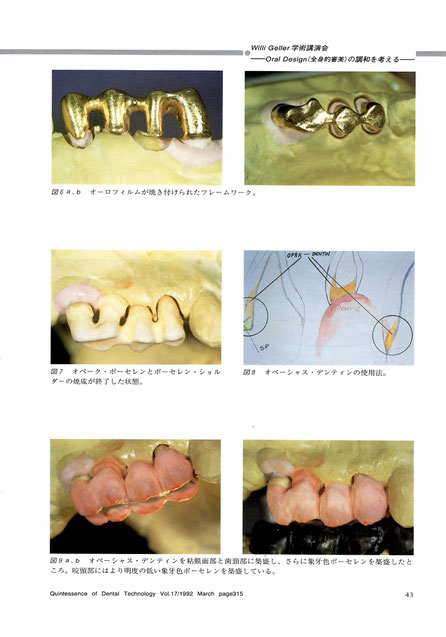

図6a オーロフィルムが焼き付けられたフレームワーク。

図6b オーロフィルムが焼き付けられたフレームワーク。

図7 オペーク・ポーセレンとポーセレンショルダーの焼成が終了した状態。

図8 オペーシャス・デンティンの使用法。

図9a, b オペーシャス・デンティンを粘膜面部と歯頚部に築盛し、さらに象牙色ポーセレンを築成したところ。咬頭部にはより明度の低い象牙色ポーセレンを築盛している。